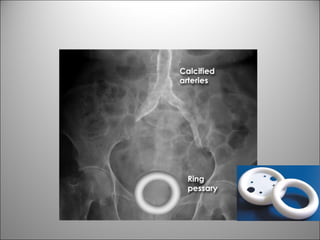

CALCIFICACIONES Y ARTEFACTOS

MIOMAS

CALCIFICACIONES AORTICAS